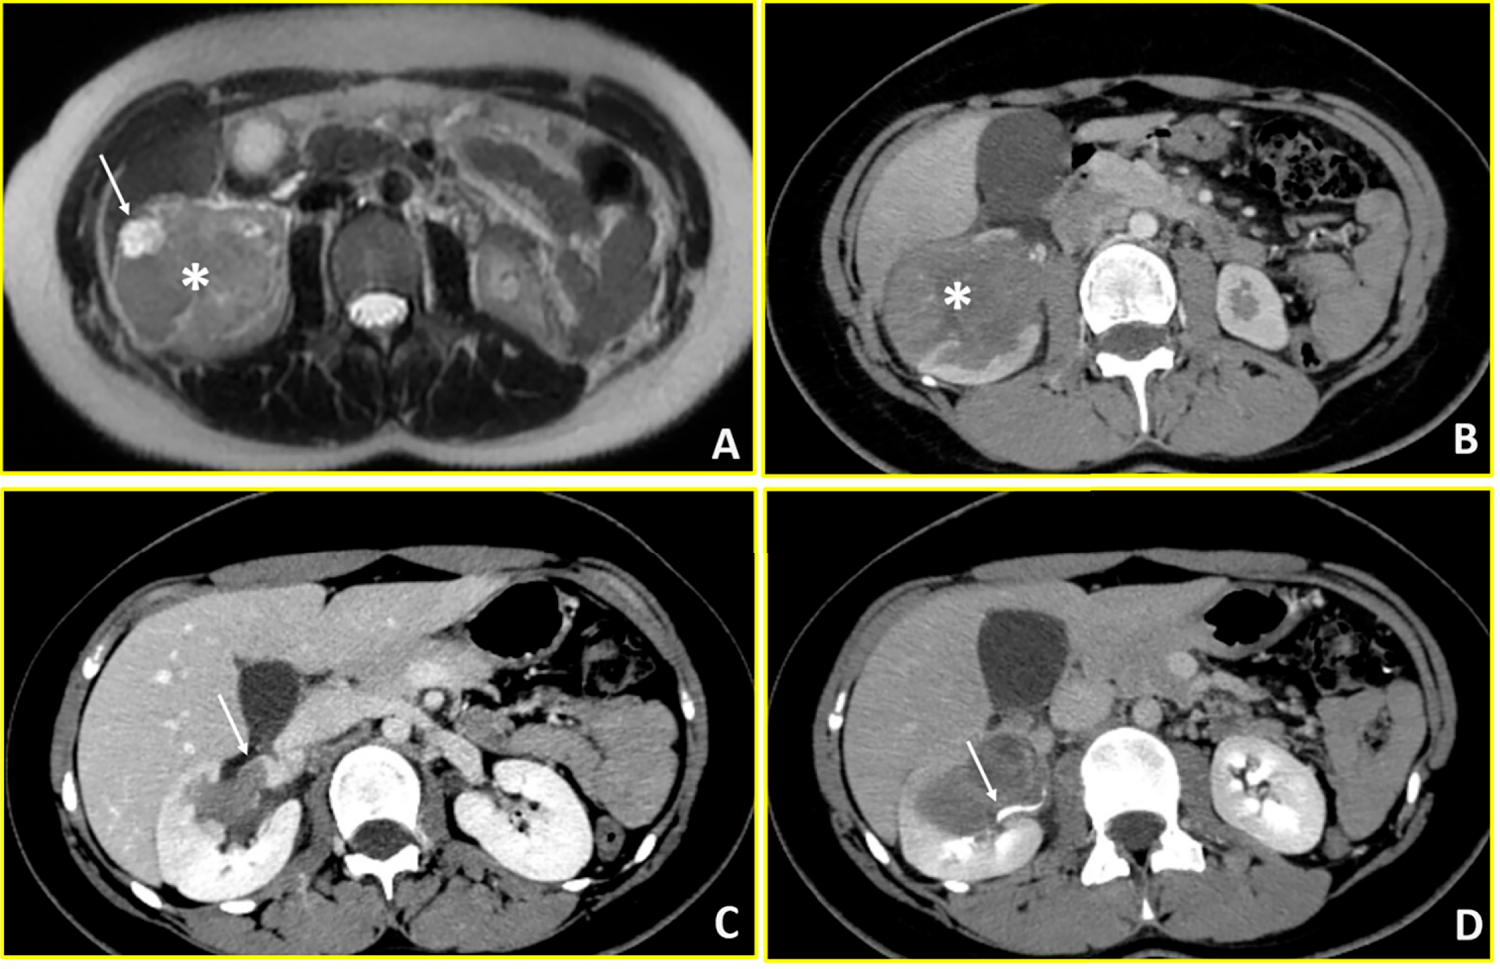

A 13-year-old female presented at the Emergency Department of San Camillo Hospital in Rome with right abdominal and lumbar pain. Abdominal ultrasonography demonstrated a 7.5 cm inferior polar lesion of the right kidney. Abdominal MRI and total body CT confirmed the presence of a voluminous, heterogeneous, expansive lesion affecting the lower middle third of the right kidney with extensive extracapsular involvement at the lower pole, in contact with the ascending colon and the sixth hepatic segment. The tumour architecture was irregularly triangular with the apex extending toward the renal hilum, causing thrombosis of an intrarenal vein branch. Internal heterogeneity was attributed to areas of hemorrhage and necrosis (Fig. 3). The CT scan showed no distant metastases. After these assessments, she was subsequently transferred to Paediatric Oncology Department of Policlinico Gemelli, to complete the diagnostic pathway and define the appropriate treatment. Following multidisciplinary discussion, a percutaneous biopsy was performed, given the patient’s age and atypical radiological features. Initial pathology suggested WT and neoadjuvant treatment was started, using vincristine and actinomycin D for 4 weeks, according to the Umbrella Protocol. However, subsequent molecular analysis identified EWSR1:FLI1 fusion transcript and histological report after complete tumour resection confirmed the diagnosis of Ewing sarcoma. After further collegial discussion involving oncologist and radiotherapist, the treatment was modified to VDC (Vincristine-Doxorubicin-Cyclophosphamide)/IE (Iphosphamide-Etoposide) protocol, including radiotherapy (RT) to the tumour bed (54 Gy on the renal lodge at the surgical site). The patient has recently begun clinical and radiological follow-up, which—given the diagnosis of sarcoma—will include a clinical examination combined with blood tests every three months during the first year, as well as local reassessment with MRI and chest X-ray.

Figure 3: Ewing sarcoma (Case 3). Multimodality imaging demonstrates a large heterogeneous mass in the right kidney with vascular and collecting system involvement. (A) T2-weighted axial MR image reveals a heterogeneous renal mass (asterisk) with extensive intralesional necrosis appearing as areas of marked hyperintensity (arrow). (B) Axial arterial-phase contrast-enhanced CT image shows a predominantly hypovascular mass (asterisk). (C) Axial venous-phase image demonstrates tumor extension into the right renal vein (arrow). (D) Axial urographic-phase image shows infiltration of the renal collecting system with involvement of the renal calyces (arrow).